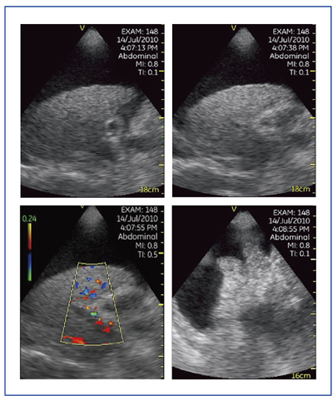

Vscanは,ディスプレイを開くだけで起動し,約10秒で検査可能となり,フタを閉じると電源がオフになる。携帯電話と同じ要領で操作可能であり,ここまで簡略化されているところがVscanの優れた点である。コントロールキーの中央のボタンでは,画像の静止と静止解除が可能であり,十字キーを操作することで視野の深さを変えることもできる。Vscanのプローブはセクタ型のみで,MI(mechanical index)値がやや低いため,超音波ゼリーを通常よりも多めに使用し,プローブの移動は平行移動と扇状の回転移動にて行う。スキャンモードは2Dモード(Bモード)とカラードプラモードが搭載されている。カラードプラ機能では,カラー感度を向上するために観察可能領域がカーソル内に限定されているため,血流を確認する際にはドプラカーソルを画面中心に固定し,視野深度を変えて目的領域をカーソル内に移動させるようにするのがポイントである。また,単一色の線が静脈,多色の線が動脈を表しているが,血流波形は得られないため,色で大まかな判別を行う。

図6は,肝硬変で門脈に血栓があり,門脈内に血流がないことが認められた症例である。Vscanのモニタは小さいが高画質であり,医師自身の観察力を高めることで,より多くの情報を得ることが可能となる。

図7は,原発性肝細胞がん破裂例である。Vscanでは,浅部の描出をやや苦手としているため,本症例においても図7 aでは腹水内の血液が点状エコーとして描出されていない。しかし,視野の中心に対象が来るようにプローブを走査し,プローブと腹水の間の距離を十分に保つことで,より細かい観察が可能となる(図7 b)。

図7 症例2:原発性肝細胞がん破裂